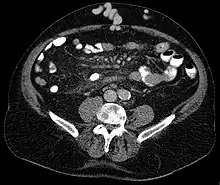

Axial CT showing portosystemic collateral circulation via the umbilical vein: caput medusae in liver cirrhosis

Caput medusae is the appearance of distended and engorged superficial epigastric veins, which are seen radiating from the umbilicus across the abdomen. The name caput medusae (Latin for "head of Medusa") originates from the apparent similarity to Medusa's head, which had venomous snakes in place of hair. It is also a sign of portal hypertension.[1] It is caused by dilation of the paraumbilical veins, which carry oxygenated blood from mother to fetus in utero and normally close within one week of birth, becoming re-canalised due to portal hypertension caused by liver failure.